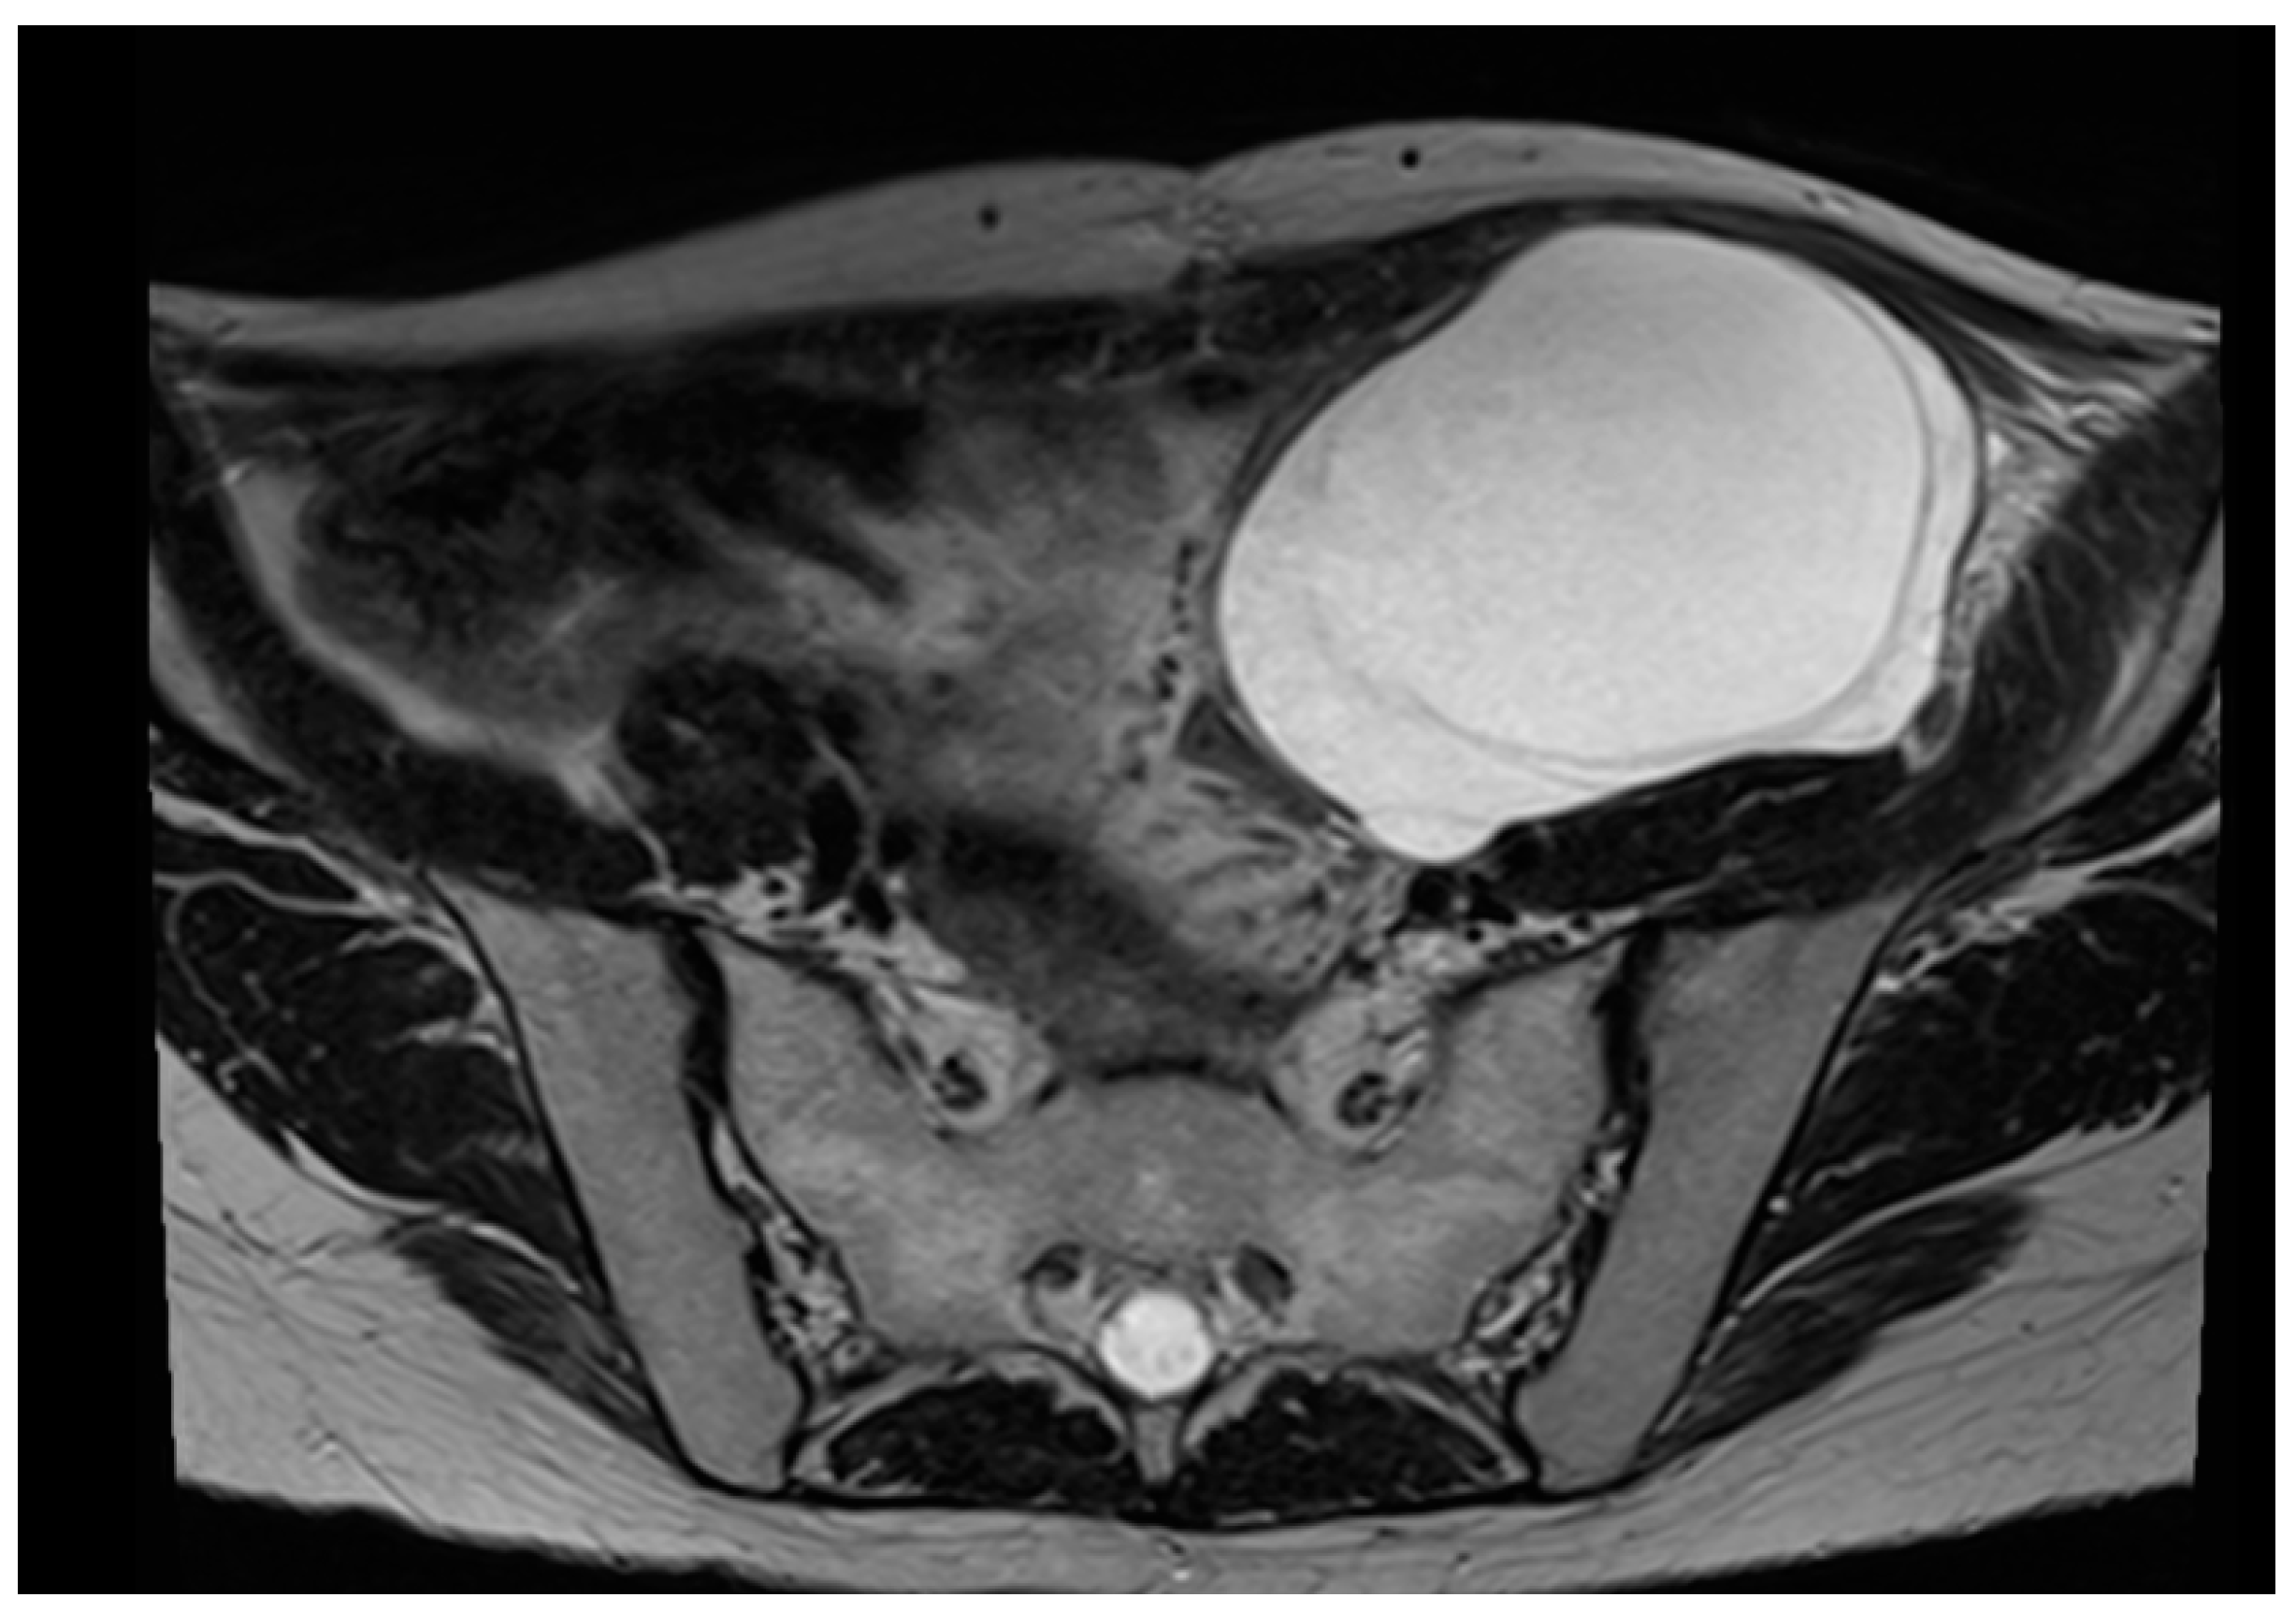

- Yan, H.; Yang, H.; Jiang, P.; Dong, L.; Zhang, Z.; Zhou, Y.; Zeng, Q.; Li, P.; Sun, Y.; Zhu, S. A Radiomics Model Based on T2WI and Clinical Indexes for Prediction of Lateral Lymph Node Metastasis in Rectal Cancer. Asian J. Surg. 2024, 47, 450–458. [Google Scholar] [CrossRef]

- Crestani, A.; Huchon, C.; Mezzadri, M.; Marchand, E.; Place, V.; Cornelis, F.; Touboul, C.; Haddad, B.; Dabi, Y.; Benifla, J.-L.; et al. A Pre-Operative Radiological Score to Predict Lymph Node Metastasis in Advanced Epithelial Ovarian Cancer. J. Gynecol. Obstet. Hum. Reprod. 2022, 51, 102464. [Google Scholar] [CrossRef] [PubMed]